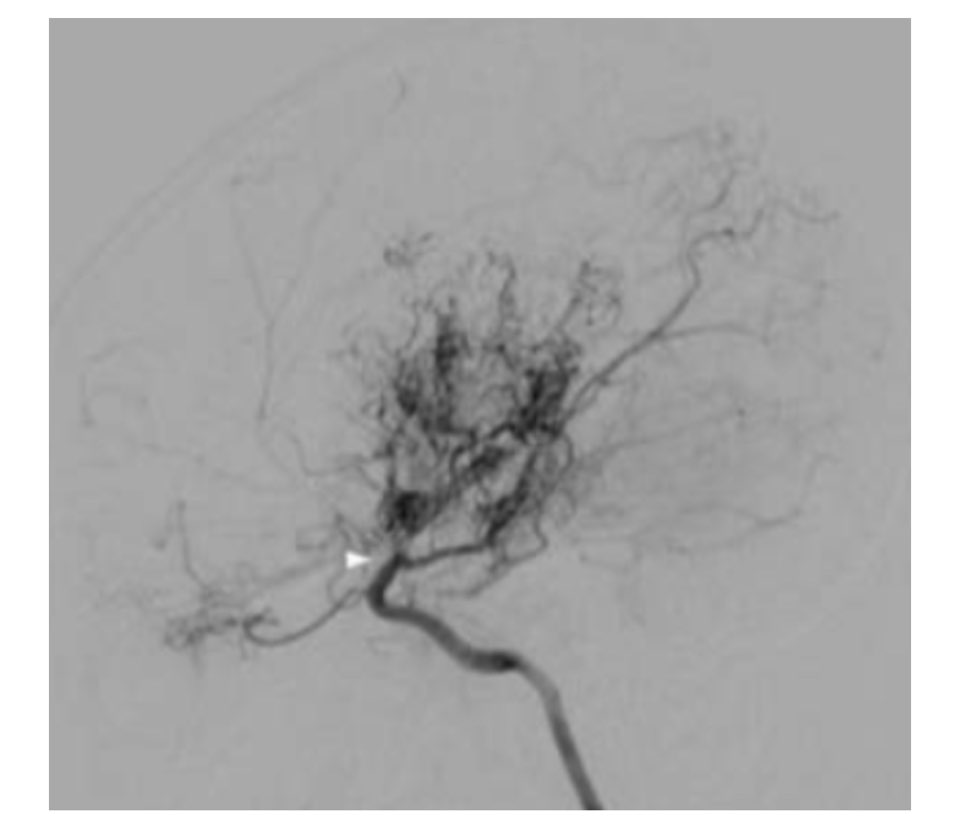

모야모야병은 대뇌에 혈류를 공급하는 데 중요한 역할을 하는 혈관과 모야모야 혈관이라는 작은 이상혈관이 내동맥 끝에서 좁아지는 질환으로 특별한 원인 없이 발생하는 것으로 알려져 있습니다.

일본 스즈키가 뇌혈관 동맥 조영상에서 '담배 연기가 피어오르는 모습'을 뜻하는 '모야모야'라는 이름이 붙었습니다.

모야모야병은 증상 의심이 가장 중요하며 CT, MRI, MRA, 뇌혈관조영술 등 영상진단이 필수입니다.